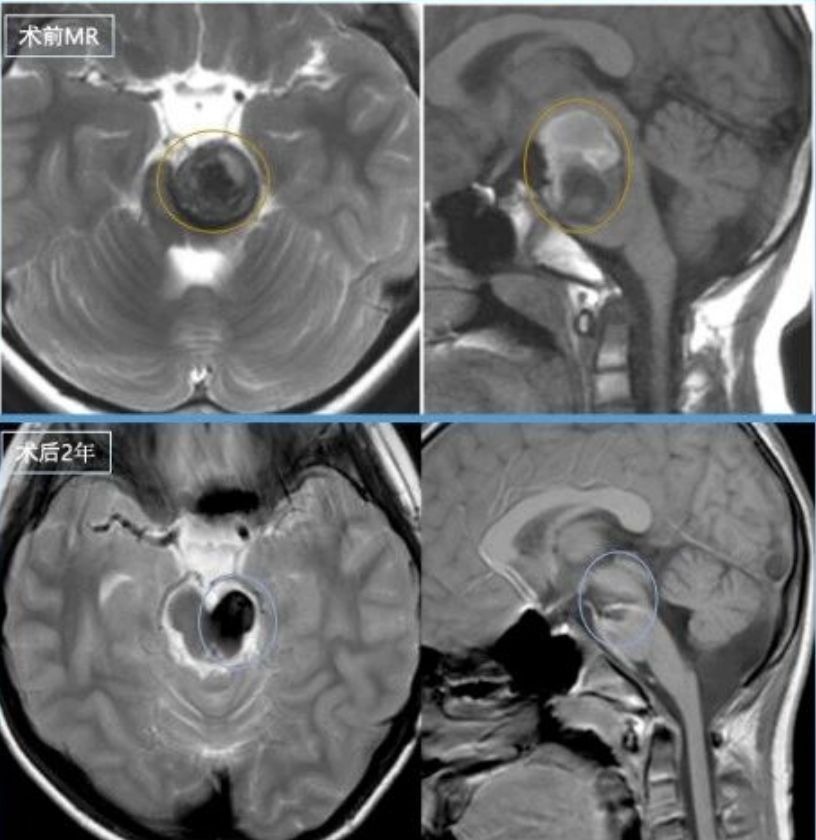

术前影像显示脑干脑桥左侧占位病变,锥体束受压,可见含铁血黄素环形成。

术后三年随访影像学检查显示无复发征象。额部手术疤痕成为患儿勇敢战胜疾病的象征,患儿恢复高活力状态,同时展现出超乎年龄的坚韧品质。